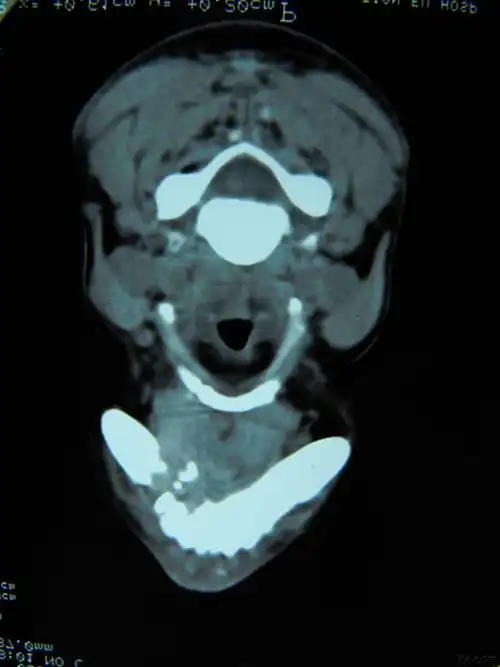

广西5龄童下颌骨长巨大肿瘤 手术成功康复出院

下颌骨右侧已发生骨吸收